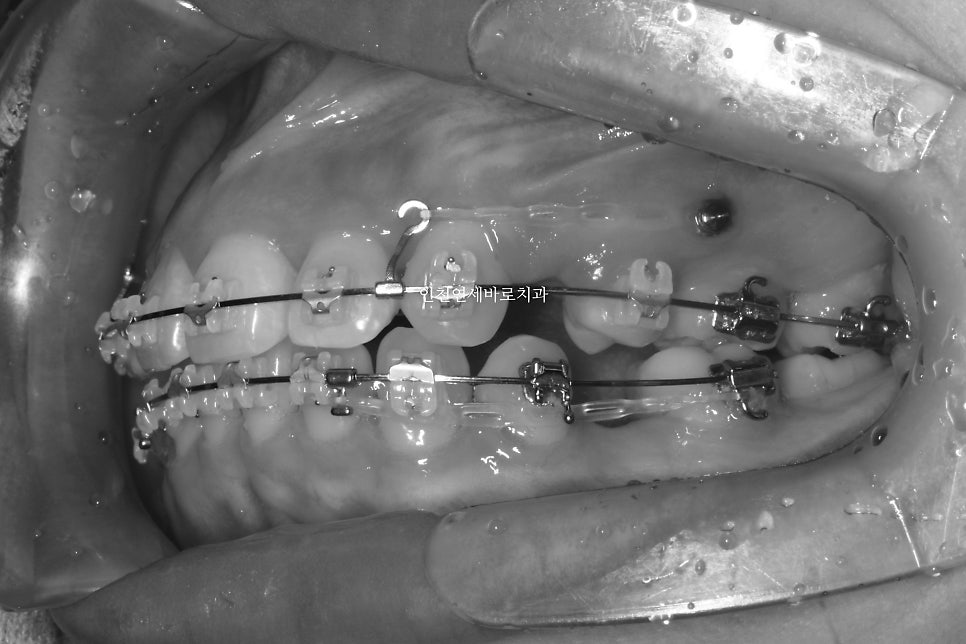

미니스크류를 식립 후 바로 찍은 사진입니다.

총 6개의 미니스크류를 식립하고 치료를 했습니다

미니스크류를 잘 이용하면 얼굴이 짧아지면서 자연스러운 입술을 만들 수 있습니다.

치료기간이 조금 더 긴편이지만, 극적인 안모변화를 얻는 경우가 많습니다